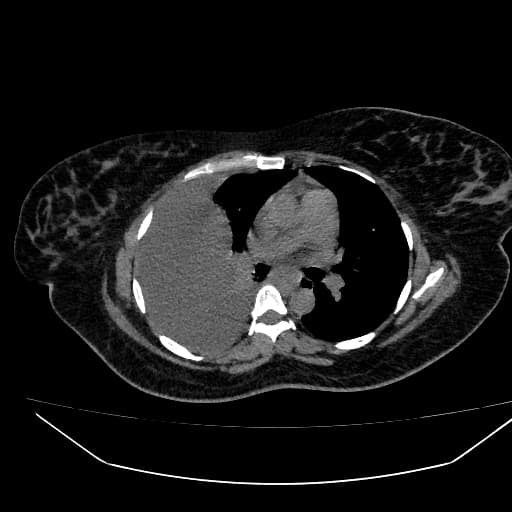

T1 in-phase

- Khối lớn, dạng thùy ở vùng trung tâm gan, tín hiệu trên T2 tăng, trên T1 giảm.

- Tăng quang không đồng nhất, chủ yếu ở vùng ngoại vi, lan rộng dần vào trung tâm ở các thì hình ảnh trễ.

- Dãn ống mật trong gan đi kèm, đặc biệt là các ống mật gan trái.

- Thấy hình ảnh sỏi túi mật (cholelithiasis).

Khối lớn ở trung tâm gan, dạng thùy, tín hiệu T2 tăng, T1 giảm. Tăng quang không đồng nhất, chủ yếu ở vùng ngoại vi, lan rộng dần vào trung tâm ở thì trễ. Có dãn ống mật trong gan đi kèm, đặc biệt là các ống mật gan trái. Hình ảnh sỏi túi mật (cholelithiasis) cũng được ghi nhận.

Hình ảnh phù hợp với ung thư tế bào gan (cholangiocarcinoma) – dạng hình thành khối trong gan (mass-forming intrahepatic type).